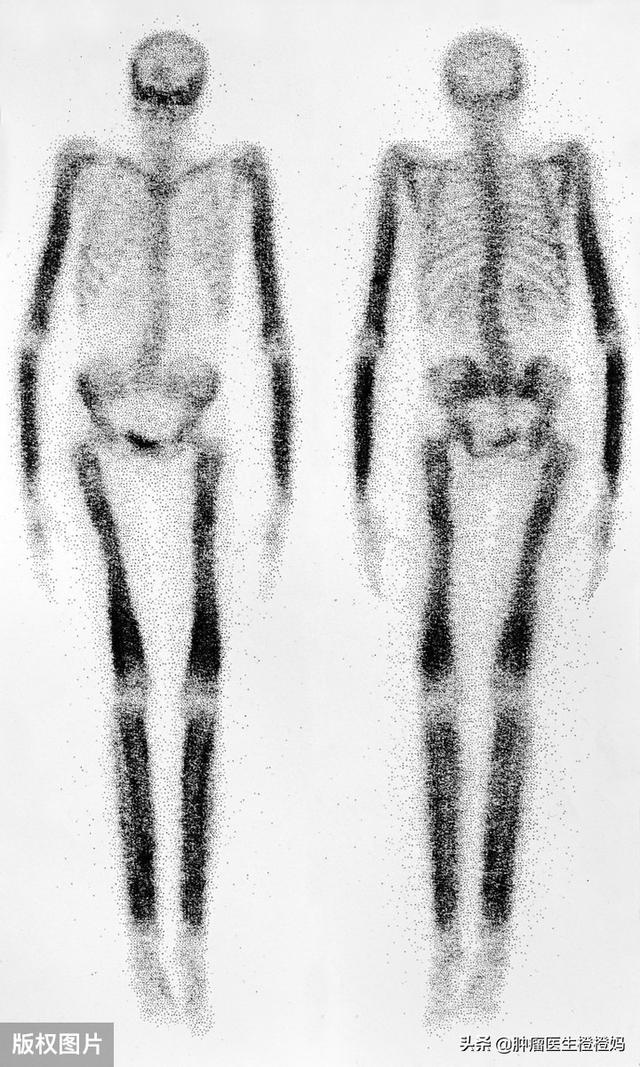

- Scintigraphie osseuse du corps entier :C'est le principal moyen de déterminer initialement la présence ou l'absence de métastases osseuses et il est généralement utilisé comme premier dépistage. C'est pourquoi, lorsqu'une tumeur maligne est diagnostiquée, votre médecin vous recommande de passer une scintigraphie osseuse.Balaie les os sur tout le corps, meilleur rapport qualité-prix. Cependant, certaines réactions inflammatoires observées lors de la scintigraphie osseuse semblent similaires à celles des métastases osseuses, de sorte que d'autres radiographies, un scanner ou une IRM sont nécessaires pour faciliter le diagnostic.

Le test le plus courant pour les métastases osseuses est la scintigraphie osseuse, qui est moins coûteuse et révèle un problème qui est ensuite confirmé par des examens d'imagerie tels que les rayons X, la tomodensitométrie et l'imagerie par résonance magnétique. Bien sûr, le PET-CT est meilleur que la scintigraphie au nucléide osseux, mais son coût est trop élevé.

Deuxièmement, sur la base des résultats de l'examen.Les métastases osseuses dues au cancer peuvent apparaître à l'imagerie comme une destruction ostéogénique ou ostéolytique. Elles sont très différentes des lésions osseuses ordinaires. En clinique, nous utilisons généralement la scintigraphie osseuse pour déterminer s'il y a des métastases osseuses.👆👆👆上图中,特别'黑'的地方可能就是骨转移!Bien entendu, si les autres examens ne révèlent aucun foyer primaire, le médecin peut décider de procéder à un examen pathologique du tissu osseux dans la région où l'on soupçonne la présence de métastases osseuses. Cet examen permet d'une part de déterminer s'il s'agit réellement d'une métastase osseuse tumorale maligne, et d'autre part de déterminer l'origine des cellules cancéreuses grâce à la coloration pathologique.